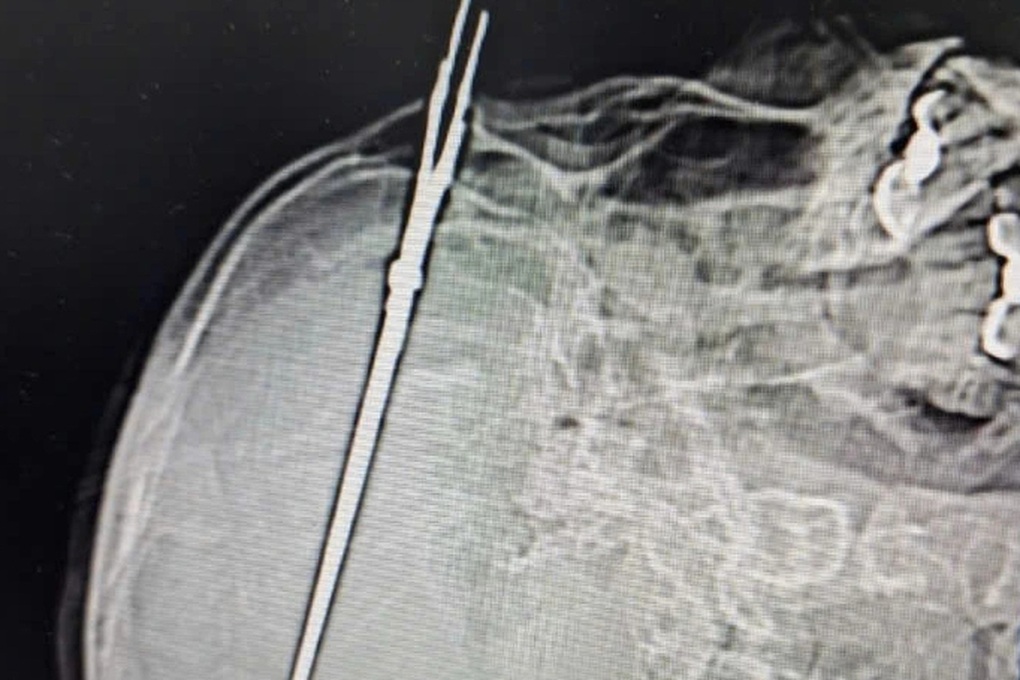

Lưỡi kéo dài 19cm cắm sâu vào sọ của nam thanh niên (Ảnh: Uy Nguyễn).

Theo bác sĩ Đồng, khoa Ngoại thần kinh tiếp nhận bệnh nhân T. và ê kíp đã mổ lấy lưỡi kéo dài 19cm cắm sâu trong sọ não. "Sau ca phẫu thuật, tình trạng của bệnh nhân tương đối ổn định và đang được theo dõi sát tại bệnh viện", bác sĩ cho hay.